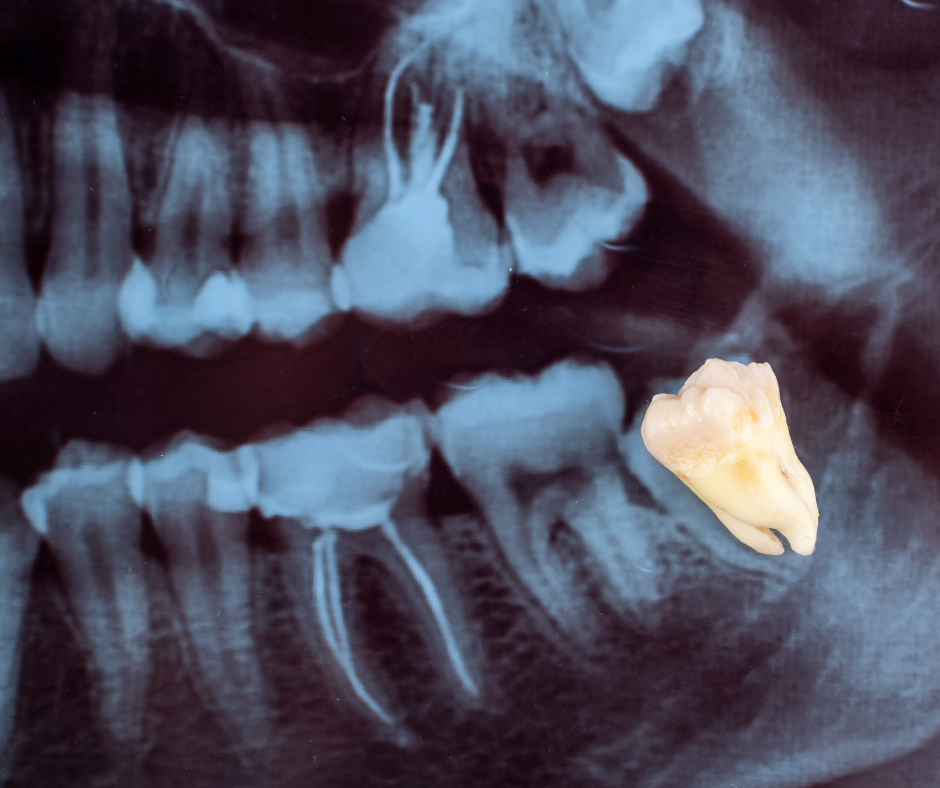

Надо ли лечить зуб мудрости или лучше сразу удалить?

стоит ли лечить зуб мудрости или проще и надёжнее сразу его удалить? Разберём этот вопрос подробно: Почему зубы мудрости часто вызывают проблемы Зубы мудрости прорезываются последними, обычно после 18–25 лет, а у многих — и значительно позже.

К этому моменту челюсть уже сформирована, и места для полноценного зуба часто просто не хватает. Из-за этого восьмые зубы нередко: растут под наклоном; прорезываются не полностью; находятся глубоко и неудобно для чистки; быстро накапливают налёт и кариес. Особенно часто проблемы с зубами мудрости появляются именно после 40–50 лет, когда ткани восстанавливаются медленнее, а иммунный ответ уже не такой активный. В каких случаях зуб мудрости имеет смысл лечить Несмотря на распространённое мнение, не каждый зуб м